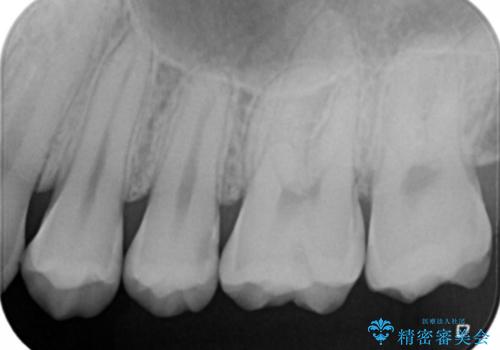

- 左上7番の虫歯治療を主訴に来院された患者様です。

虫歯の範囲が広かったので切削量・形態を考慮し、セラミッククラウンでの治療を計画しました。

虫歯の範囲が広い場合、大きく削る必要があるので部分的に詰めるインレーではなく、クラウンでの治療になることがあります。